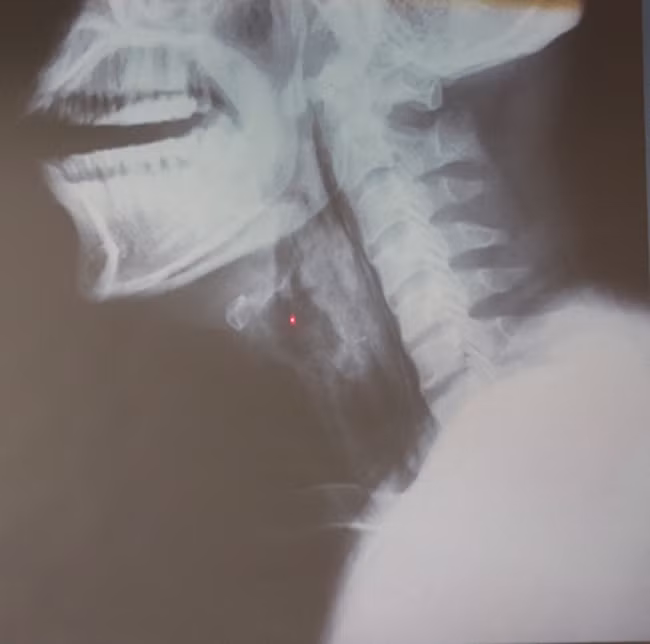

Cổ họng anh D. bị phù nề và tổn thương nặng vì bệnh viêm thanh thiệt cấp.

Sau khi làm các xét nghiệm, các bác sĩ phát hiện, anh D. không phải bị mắc xương cá như người nhà khai, mà lại bị viêm phù nề thanh thiệt cấp. Đây là căn bệnh nguy hiểm có thể lấy đi tính mạng chỉ trong một giờ nếu bệnh trở nặng.

Một người bị viêm “nắp” thanh quản cấp phù nề thì “nắp” thanh quản không thể “bật” lên, nó đóng chặt khiến bệnh nhân không thể thở được, gây suy hô hấp.

Nắp thanh quản.